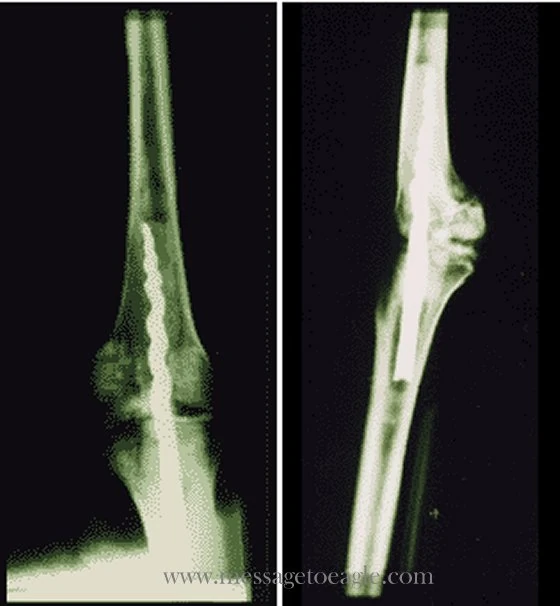

X-ray of Usermontu's left knee

In August 1995, an x-ray was performed on the mummy which found that it had undergone a sophisticated procedure in which a orthopedic pin had been inserted into the left knee. From the x-ray alone it was thought that the pin was a modern addition in order to keep the body parts in tact because of how advanced the surgical procedure was. In 1998, a team of scientists found traces of ancient organic resin that held the pin in place, analogous to modern bone cement.

The metallic composition of the corkscrew pin is pure iron, it was put in before the man was mummified, but if it was inserted while he was still living or just after he died is still unknown. Never before has an Egyptian mummy shown anything similar.